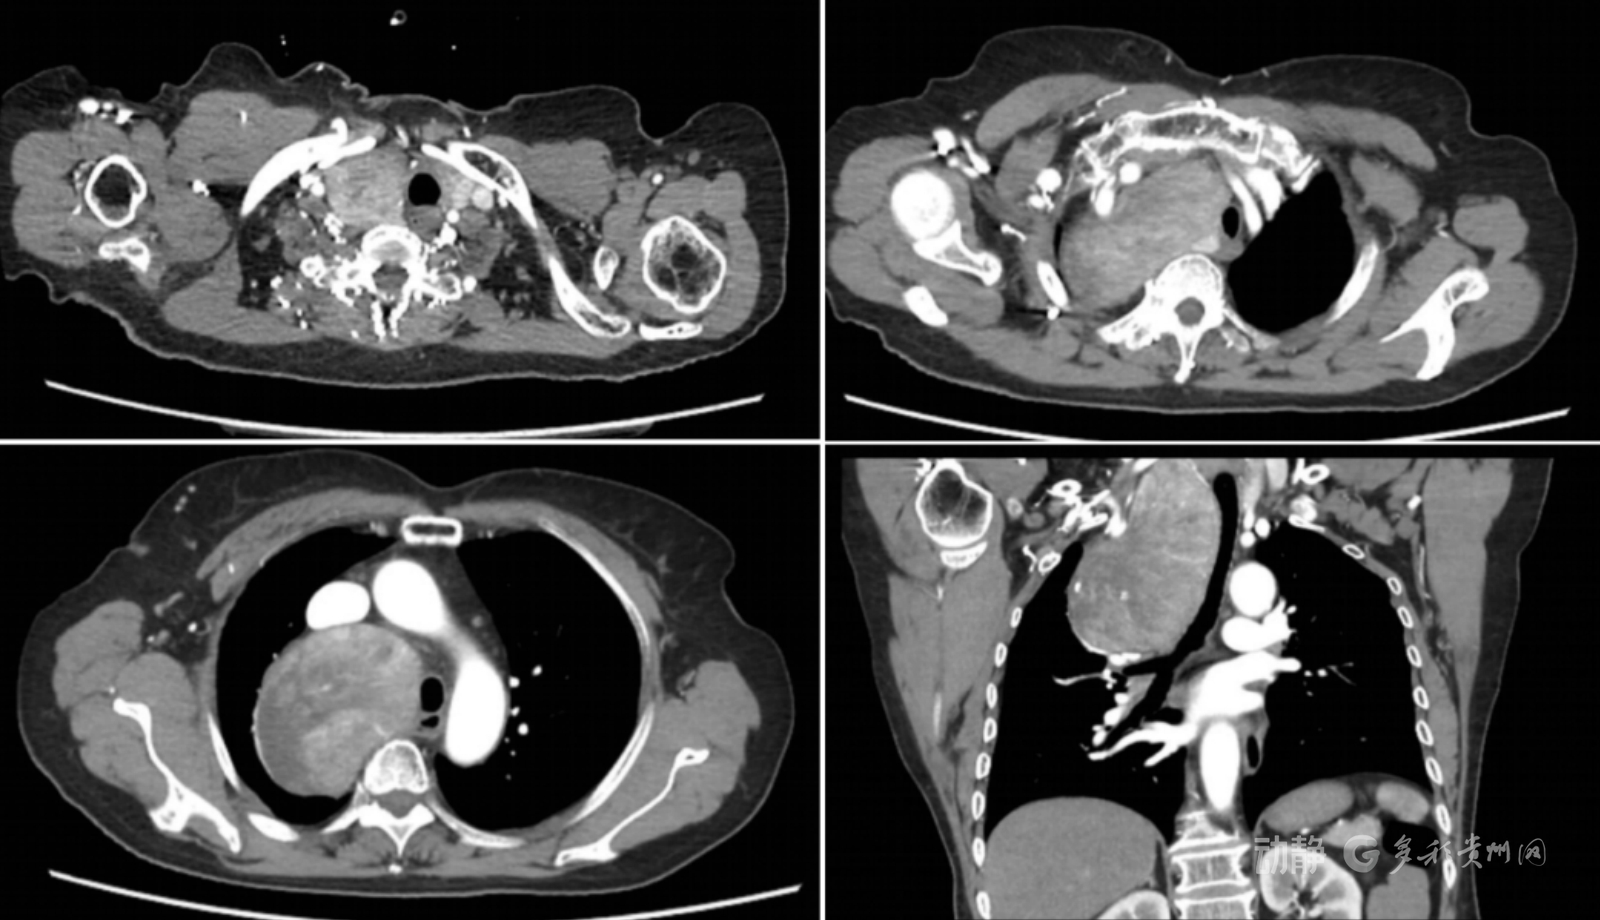

“检查发现胸腔有这么大的肿瘤,我很着急呀。”68岁的钟阿姨回忆,自己因反复胸闷、咳嗽伴喘息在外院查出右前上纵隔有一巨大肿物,大小约13×10×10cm,堪比成年人的拳头。影像显示,肿瘤已明显压迫气管及邻近血管,随时可能引发呼吸困难、循环障碍。更令人担忧的是,她还合并双肺肺气肿、肺大疱等基础疾病。